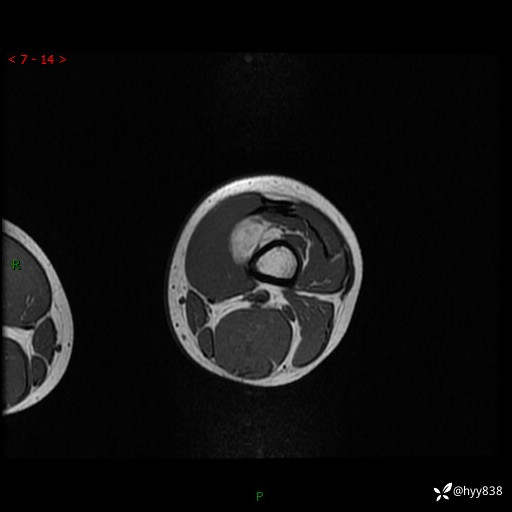

现病史:患儿3天前无意中被发现其左大腿有一包块,约鸡蛋大小,包块表面皮肤无红肿、触痛,无发热、破溃等,患儿家属当时未做特殊处理,经观察发现包块未见消退,今携患儿来我院就诊,门诊医师以“左大腿包块”收入院。 病程中,患儿神清,精神可,饮食睡眠正常,大小便通畅,体力体重无明显改变。

左大腿MRI平扫+增强